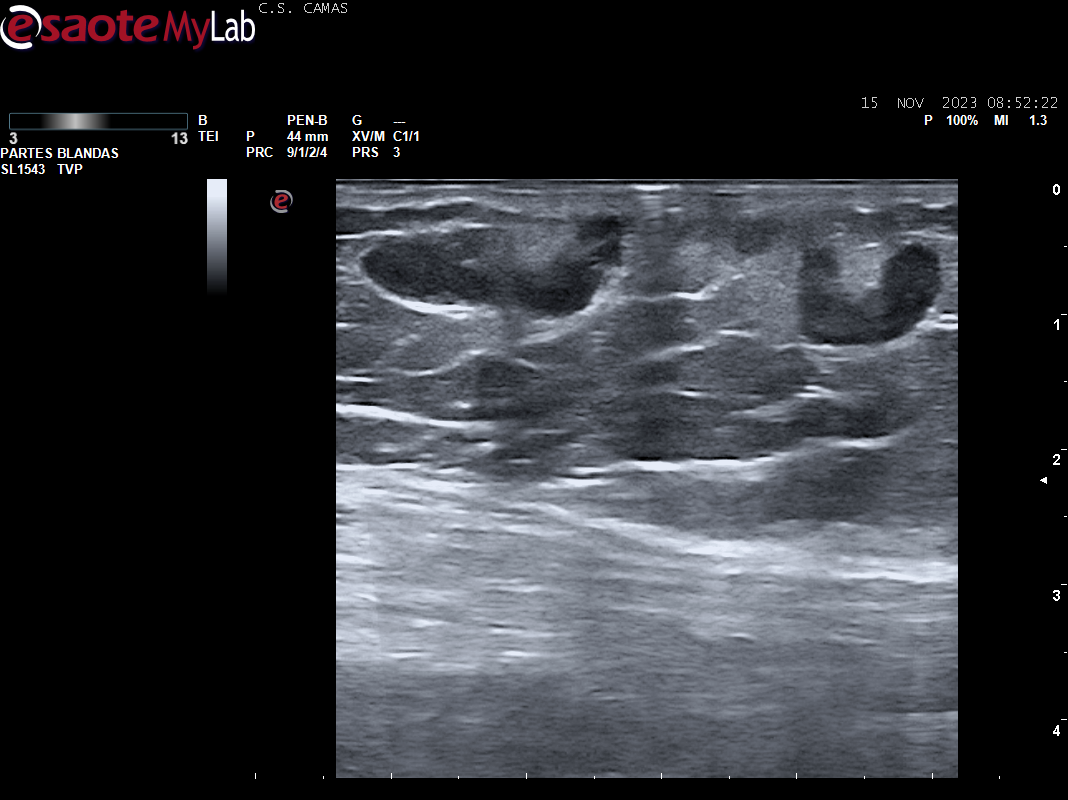

A la exploración se aprecia cordón varicoso en cara interna del muslo izq. Se realiza POCUS en consulta para descartar la presencia de TVP.

Ecografia vascular cara interna del muslo izq: Trombosis de todo el recorrido de la safena izq con dolor al paso de la sonda por colaterales inferiores que colapsan. Presenta además en zona del cayado de la safena imagen heterogenea sin apreciar la llegada de la safena a la femoral común compatible con arrancamiento de la misma.

Trombosis de todo el recorrido de la safena interna izquierda con tromboflebitis de las colaterales inferiores que concuerda con el diagnóstico hospitalario.